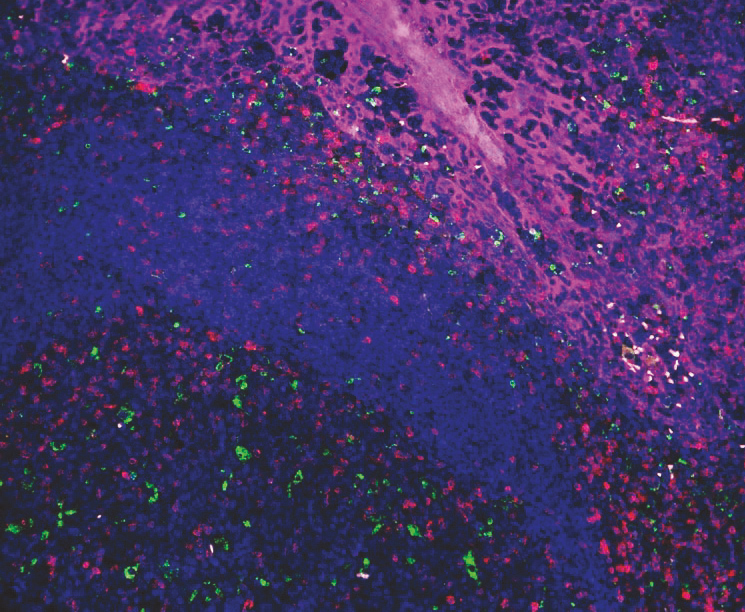

☝上图为:使用VectaPlex™进行六轮染色后的合成图像。 |

样本为扁桃体FFPE: 3种小鼠来源的一抗,分别为CD3 (红色), CD68 (绿色), AE1/AE3 (紫色), 蓝色为DAPI染色。使用Opal 3-Plex TSA试剂盒进行检测。 |